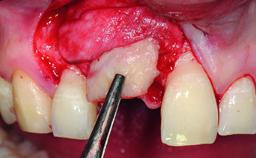

Bone Augmentation Horizontal|Simultaneous|Staged

Augmentation Materials Autogenous chips|Xenogenous|Membrane

Soft Tissue Grafting Staged

Bone Volume Deficient horizontally, requiring prior grafting